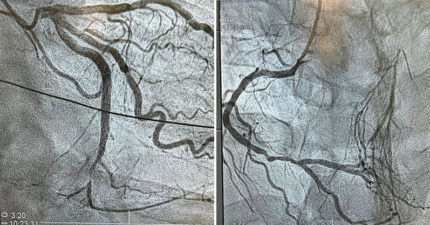

女童蛀牙「心臟瓣膜被細菌吃掉」 醫示警:死亡率比先天性心臟病還高

遠超乳癌!心血管疾病成「女性頭號死因」 4症狀快就醫